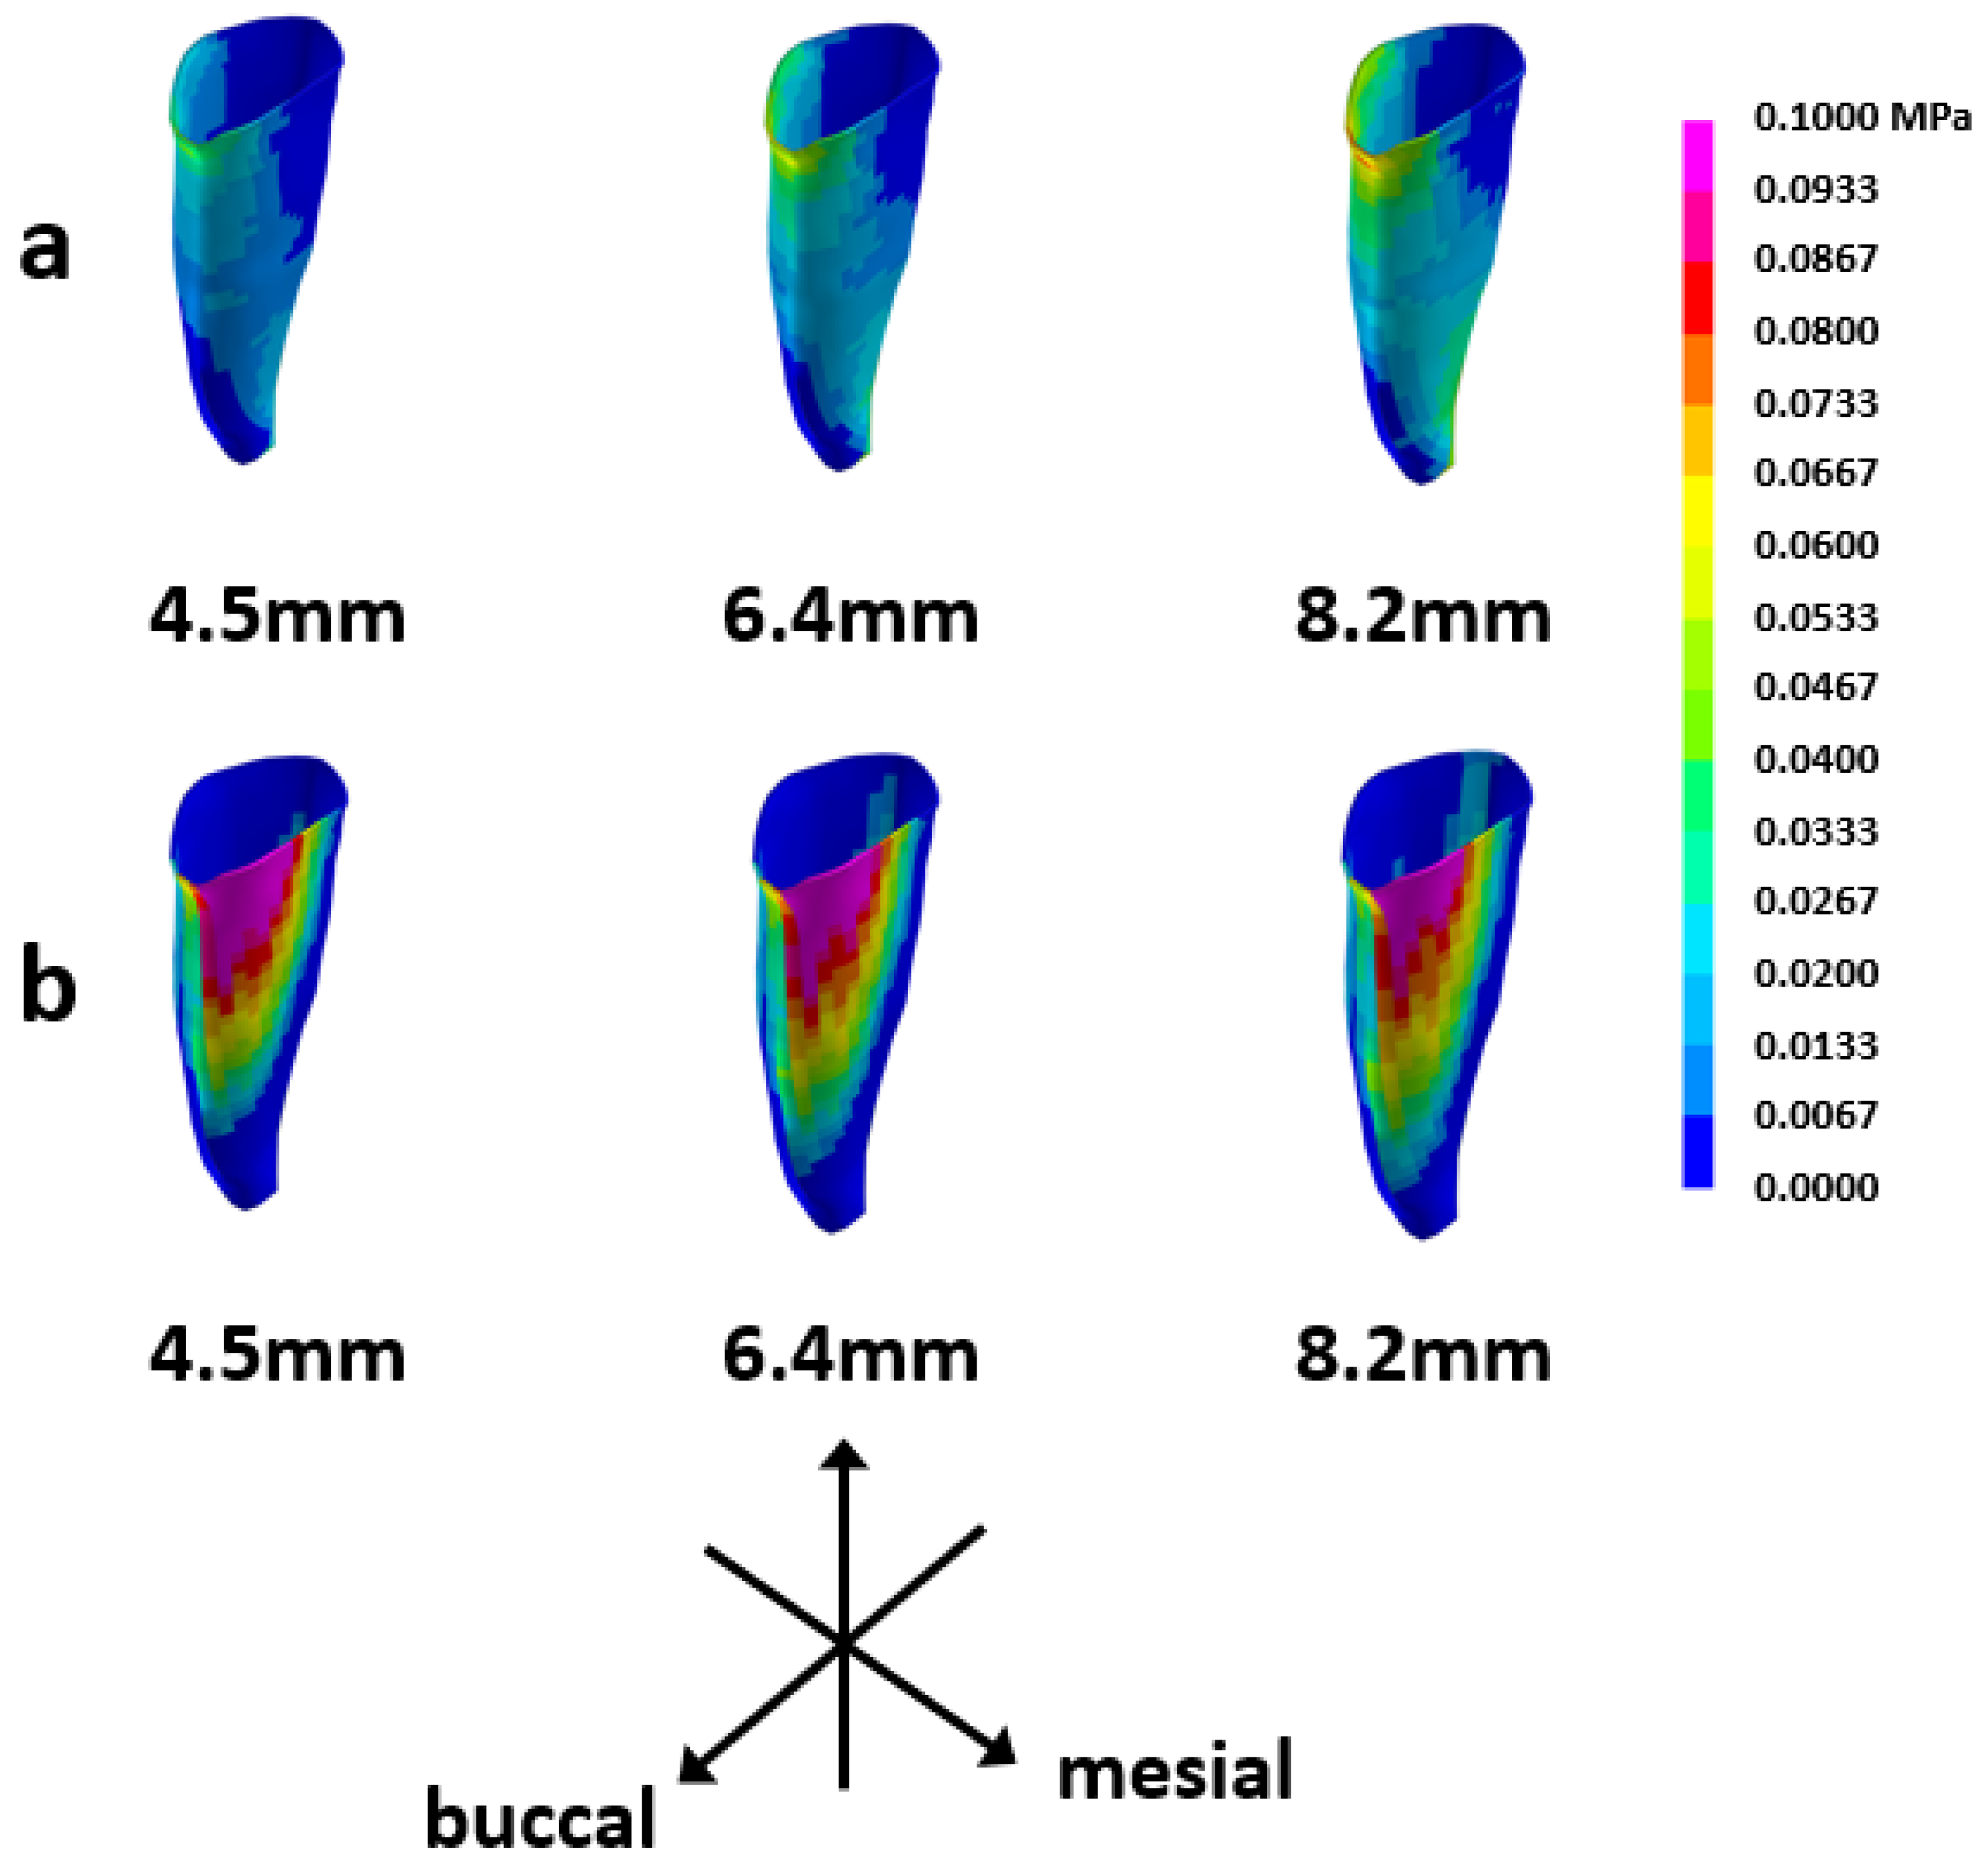

3.3. Tensile Stress Distribution in the PDL

3.4. Compressive Stress Distribution in the PDL